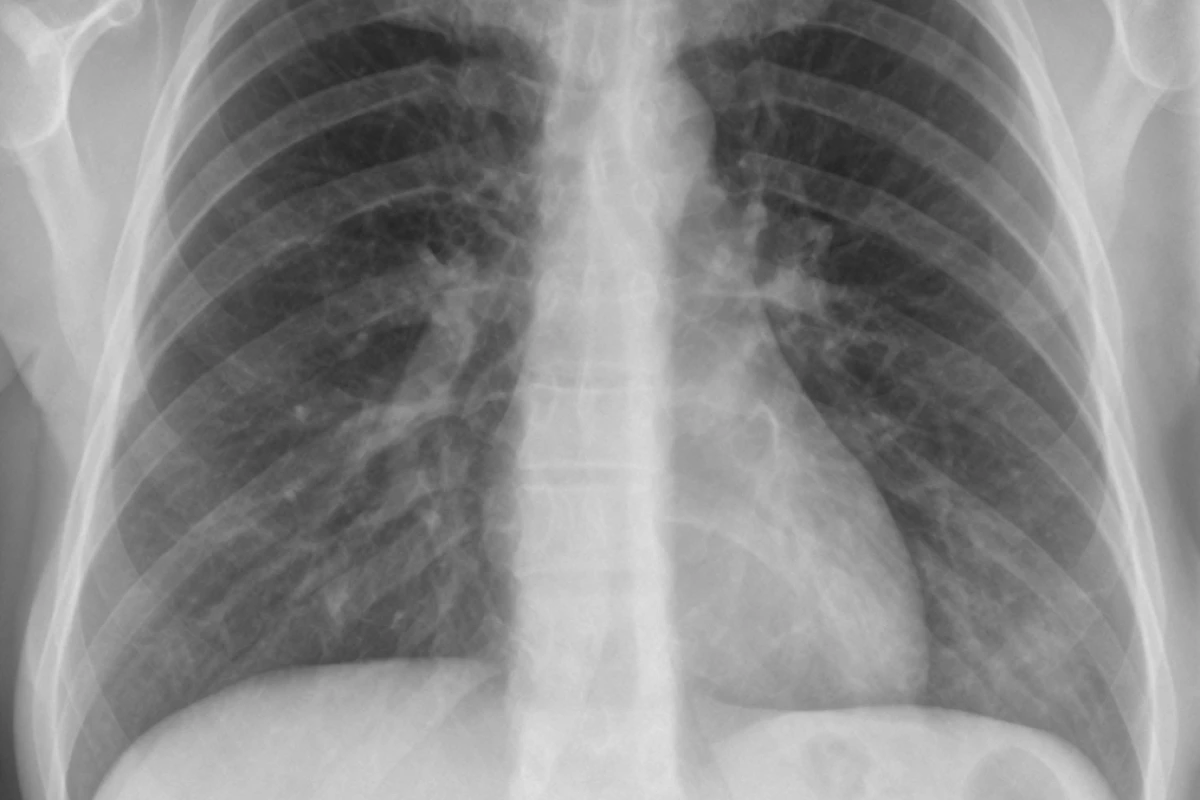

Lung Cancer Management

Lung cancer treatment depends on the type and stage. Surgery, radiation, and chemotherapy are traditional options.

Targeted therapies and immunotherapy have improved survival for many patients. These drugs attack cancer cells based on their genetic makeup or boost the immune system.

Pulmonologists often manage the respiratory symptoms of cancer and complications of treatment, such as fluid buildup.